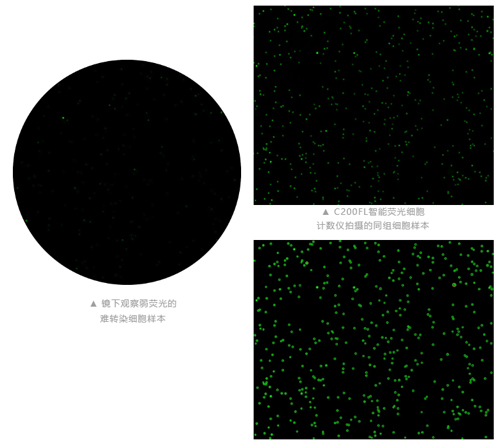

精準(zhǔn)識(shí)別PBMC

當(dāng)樣本中存在紅細(xì)胞/血小板或其他無核雜質(zhì)污染時(shí),AOPI熒光計(jì)數(shù)有其明顯優(yōu)勢(shì)。

明場(chǎng)臺(tái)盼藍(lán)計(jì)數(shù)場(chǎng)景

脾臟原代細(xì)胞與臺(tái)盼藍(lán)染液,1:1混合后計(jì)數(shù)。

弱轉(zhuǎn)染率應(yīng)用場(chǎng)景